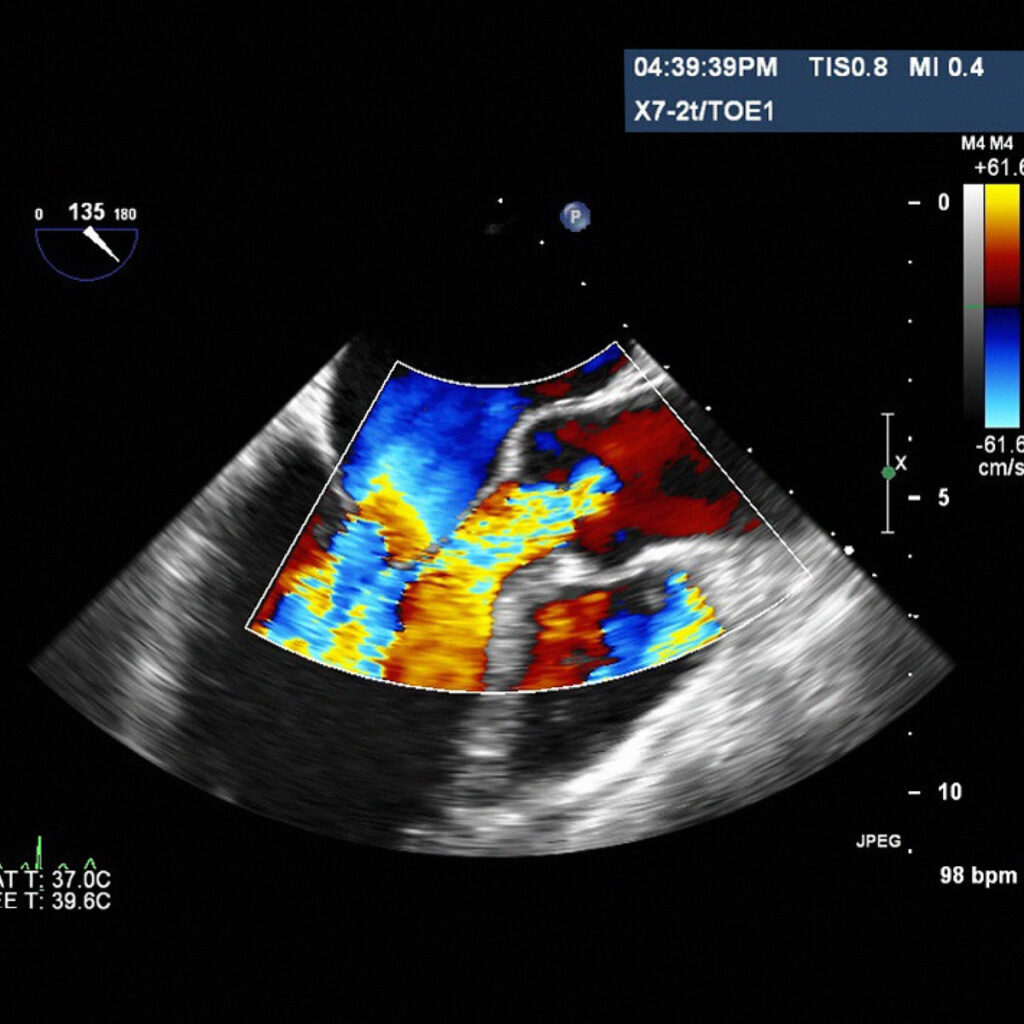

L’ecocardiogramma è un’ecografia del cuore, che attraverso l’utilizzo di ultrasuoni, ci da informazioni morfologiche e funzionali della pompa cardiaca.

È possibile pertanto valutare le dimensioni, gli spessori e la contrattilità delle camere cardiache, le valvole e il pericardio.